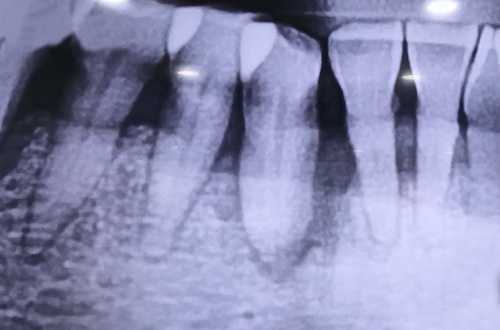

풍치로 인한 오른쪽 아래 송곳니의 통증으로 방문하신 환자분이십니다.

송곳니 주변 잇몸뼈들이 많이 녹아내려 치아를 단단하게 잡지 못하는 상태셨습니다.

송곳니 주변으로 염증이 발생하였고 흔들림이 심한 치아를 발치한 뒤 염증을

제거하고 뼈이식을 병행하여 임플란트를 당일에 바로 식립해 드렸습니다.